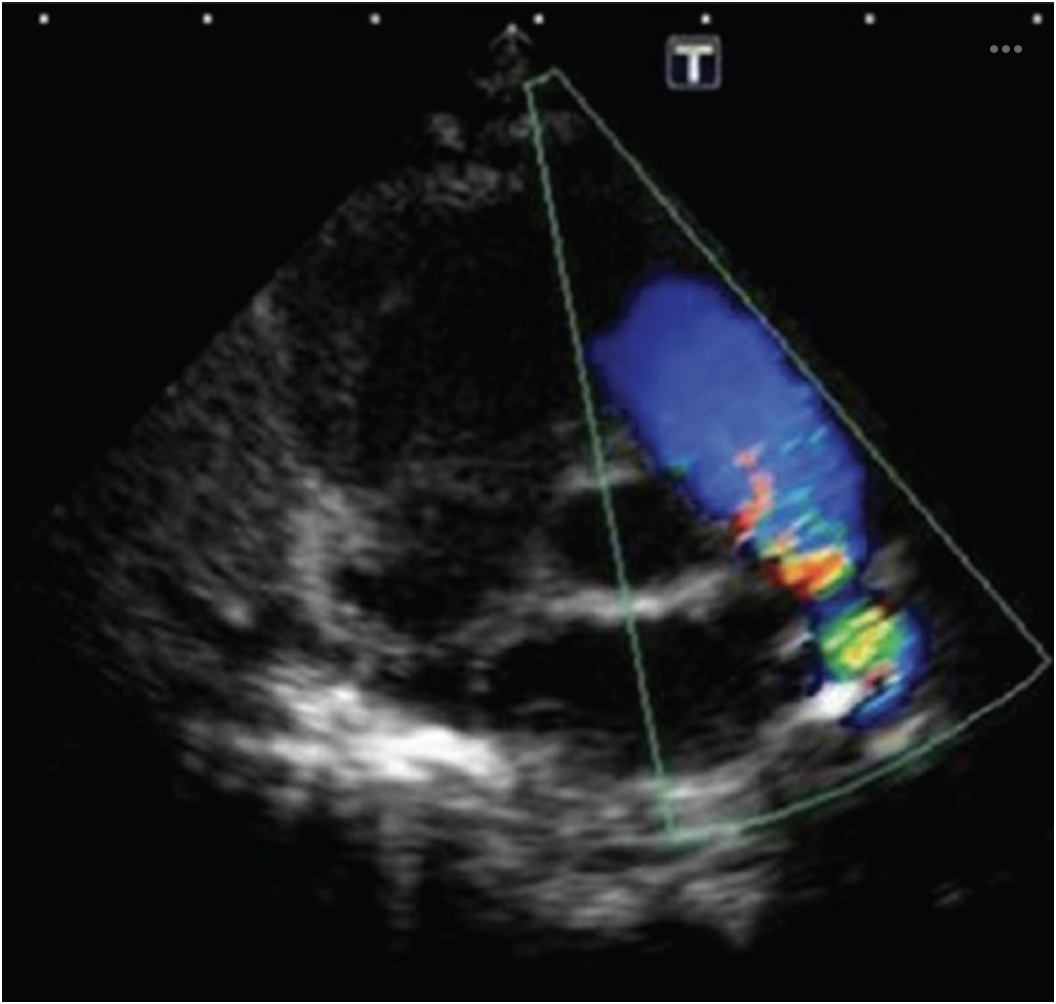

What structure in this image is being evaluated with color flow Doppler?

a) RVOT

b) RVIT

c) LVIT

d) LVOT

A